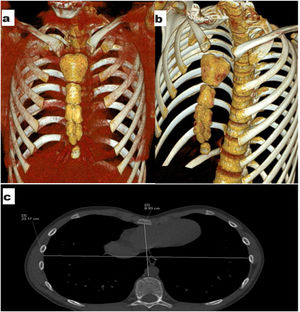

A 10-year-old male patient was admitted to the thoracic surgery outpatient clinic because of a collapsed chest wall. The chest computed tomography (CT) scan showed an appearance compatible with pectus excavatum, which can be considered mild according to the Haller Index. A honeycomb sternum, a rare variation of the sternum, was noticed on chest CT imaging (Fig. 1).

The association of honeycomb sternum with pectus excavatum has not been reported in the literature. New studies on whether this rare sternal variation can cause pectus excavatum at an early age may be important in clarifying the issue.